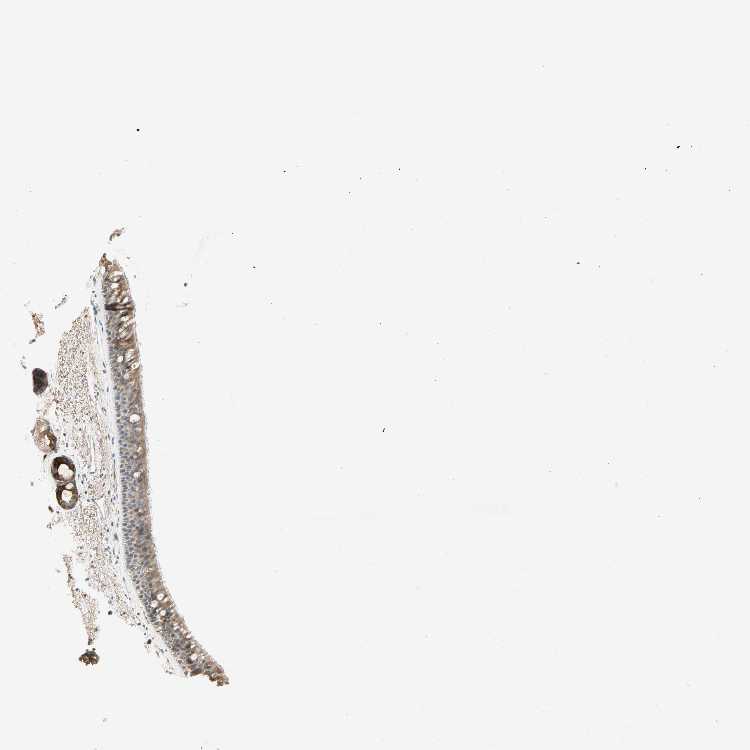

PTH1R